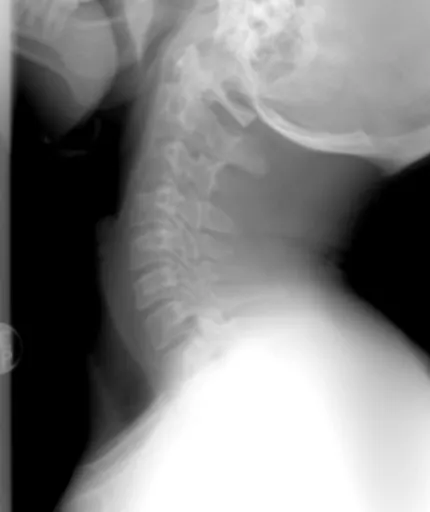

### 병원에 가면 어떤 검사를 받게 되나요?

병원에서는 엑스레이, MRI, CT 등의 영상 검사를 통해 척추 질환 여부를 확인할 수 있습니다. 또한, 신경학적 검사를 통해 신경 손상 여부를 평가할 수 있습니다.